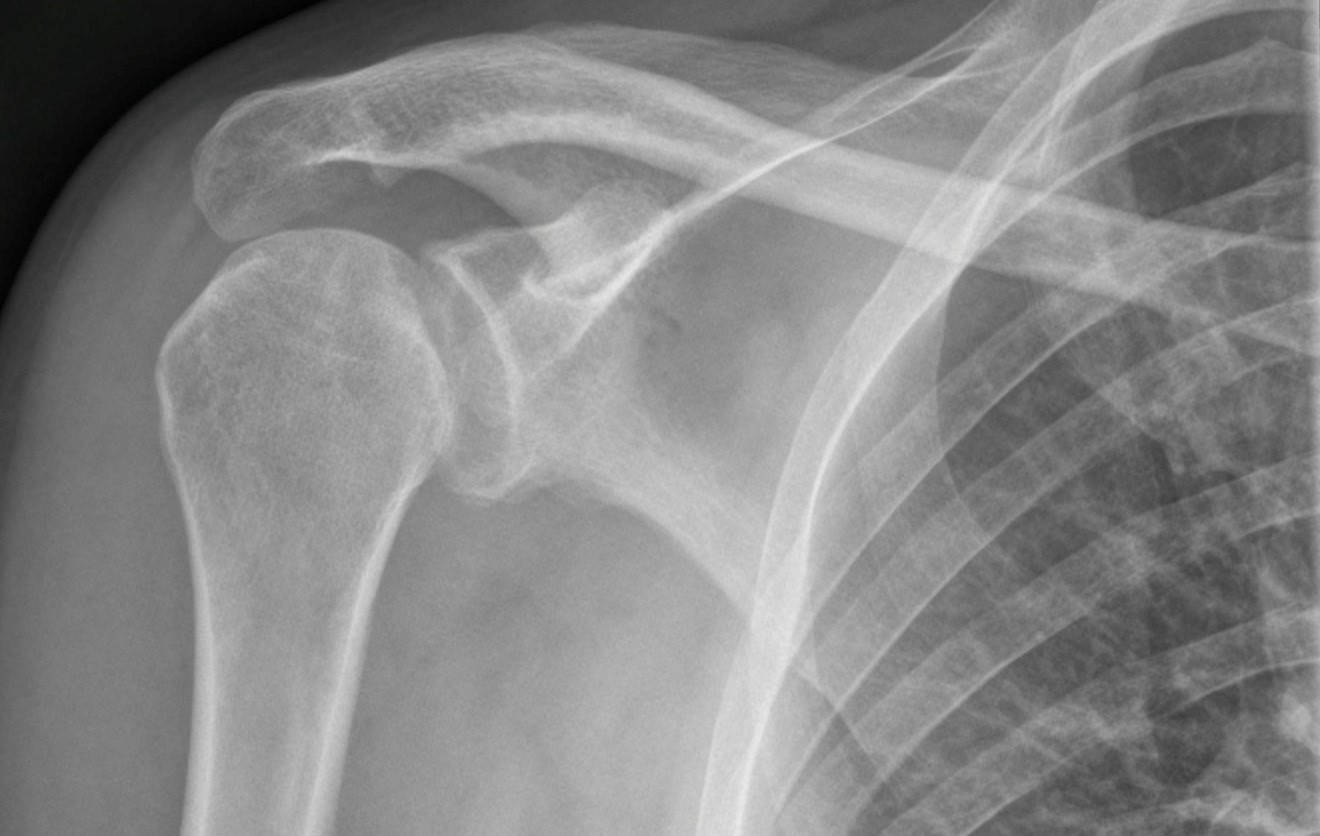

X Ray Shoulder Joint Dislocation . a health care provider inspects the affected area for tenderness, swelling or deformity and checks for signs. posterior shoulder dislocations are far less common than anterior shoulder dislocations and can be difficult to identify if only ap projections are. the shoulder joint is the most regularly dislocated joint in the body. an overview of shoulder dislocations, including anatomy, clinical features, anterior vs posterior, shoulder x. The glenohumeral joint will be. anterior shoulder dislocation is by far the commonest type of dislocation and usually results from forced abduction, external. The shoulder can dislocate forward, backward, or downward, and.

Anterior shoulder dislocation Image X Ray Shoulder Joint Dislocation anterior shoulder dislocation is by far the commonest type of dislocation and usually results from forced abduction, external. posterior shoulder dislocations are far less common than anterior shoulder dislocations and can be difficult to identify if only ap projections are. the shoulder joint is the most regularly dislocated joint in the body. The shoulder can dislocate forward,. X Ray Shoulder Joint Dislocation.